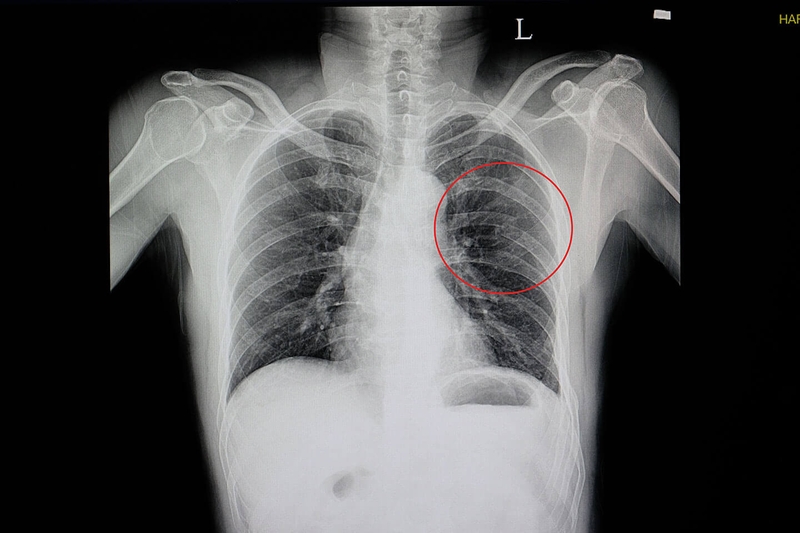

Để chẩn đoán rạn xương sườn, thường cần thực hiện các phương pháp hình ảnh như X-quang hoặc cắt lớp vi tính (CT). Điều trị thường bao gồm hỗ trợ đau, giữ cho vùng bị tổn thương ổn định và thời gian để lành sẽ thường cần thiết. Bài viết sau của Nhà thuốc Long Châu sẽ cung cấp thông tin chi tiết nhất về tình trạng này.